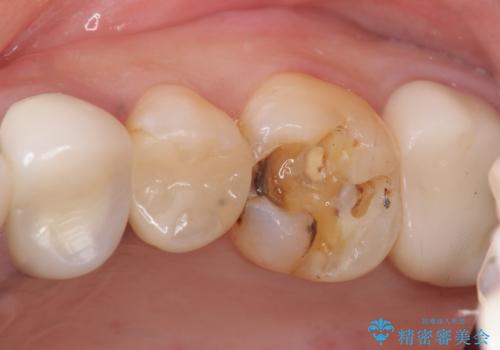

- 奥歯がたまにしみることを主訴に来院された患者様です。

精査したところ、奥歯のメタルインレー(銀の詰め物)の下でう蝕が広がっていました。

う蝕を丁寧に除去したのち、セラミックインレーによる補綴治療を行いました。